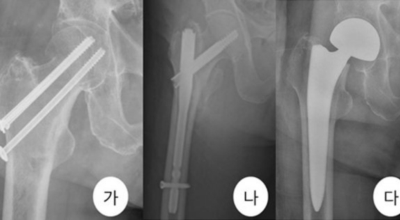

고관절 통증 치료에는 크게 약물 치료와 물리 치료가 있습니다. 고관절염의 진행을 늦추거나 증상을 완화하기 위한 목적으로 항염증제 및 진통제를 투여합니다. 고관절 통증을 조기에 치료하면 약물치료 외에 물리치료로 약 50% 정도 큰 효과를 볼 수 있습니다. 게다가, 보통 고관절 증상 관리에 도움이 되는 요가, 수영, 스트레칭은 고관절 예방과 치료에 도움이 됩니다.